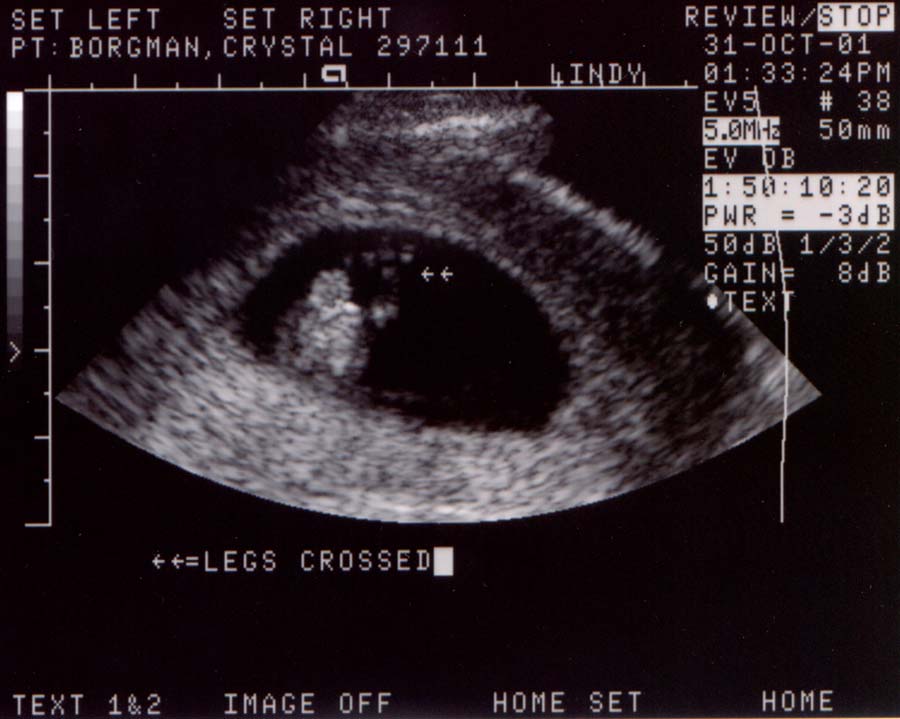

First ultrasound.

The baby looks great! It was moving around and having

a good old time. It measured at 10 weeks and 4 days,

or 37 millimeters (about 1 1/2 inches), which is just

about right. The heart rate was 188 bpm and very strong.

Looks like we've got a keeper.

Ultrasound Pictures:

Photo from top of

head looking down, baby's legs are crossed

Large

- 900x720 pixels / 66.1K

Small

- 450x360 pixels / 28.2K

head looking down, hands are together

- 900x700 pixels / 68K

- 450x350 pixels / 28.8K